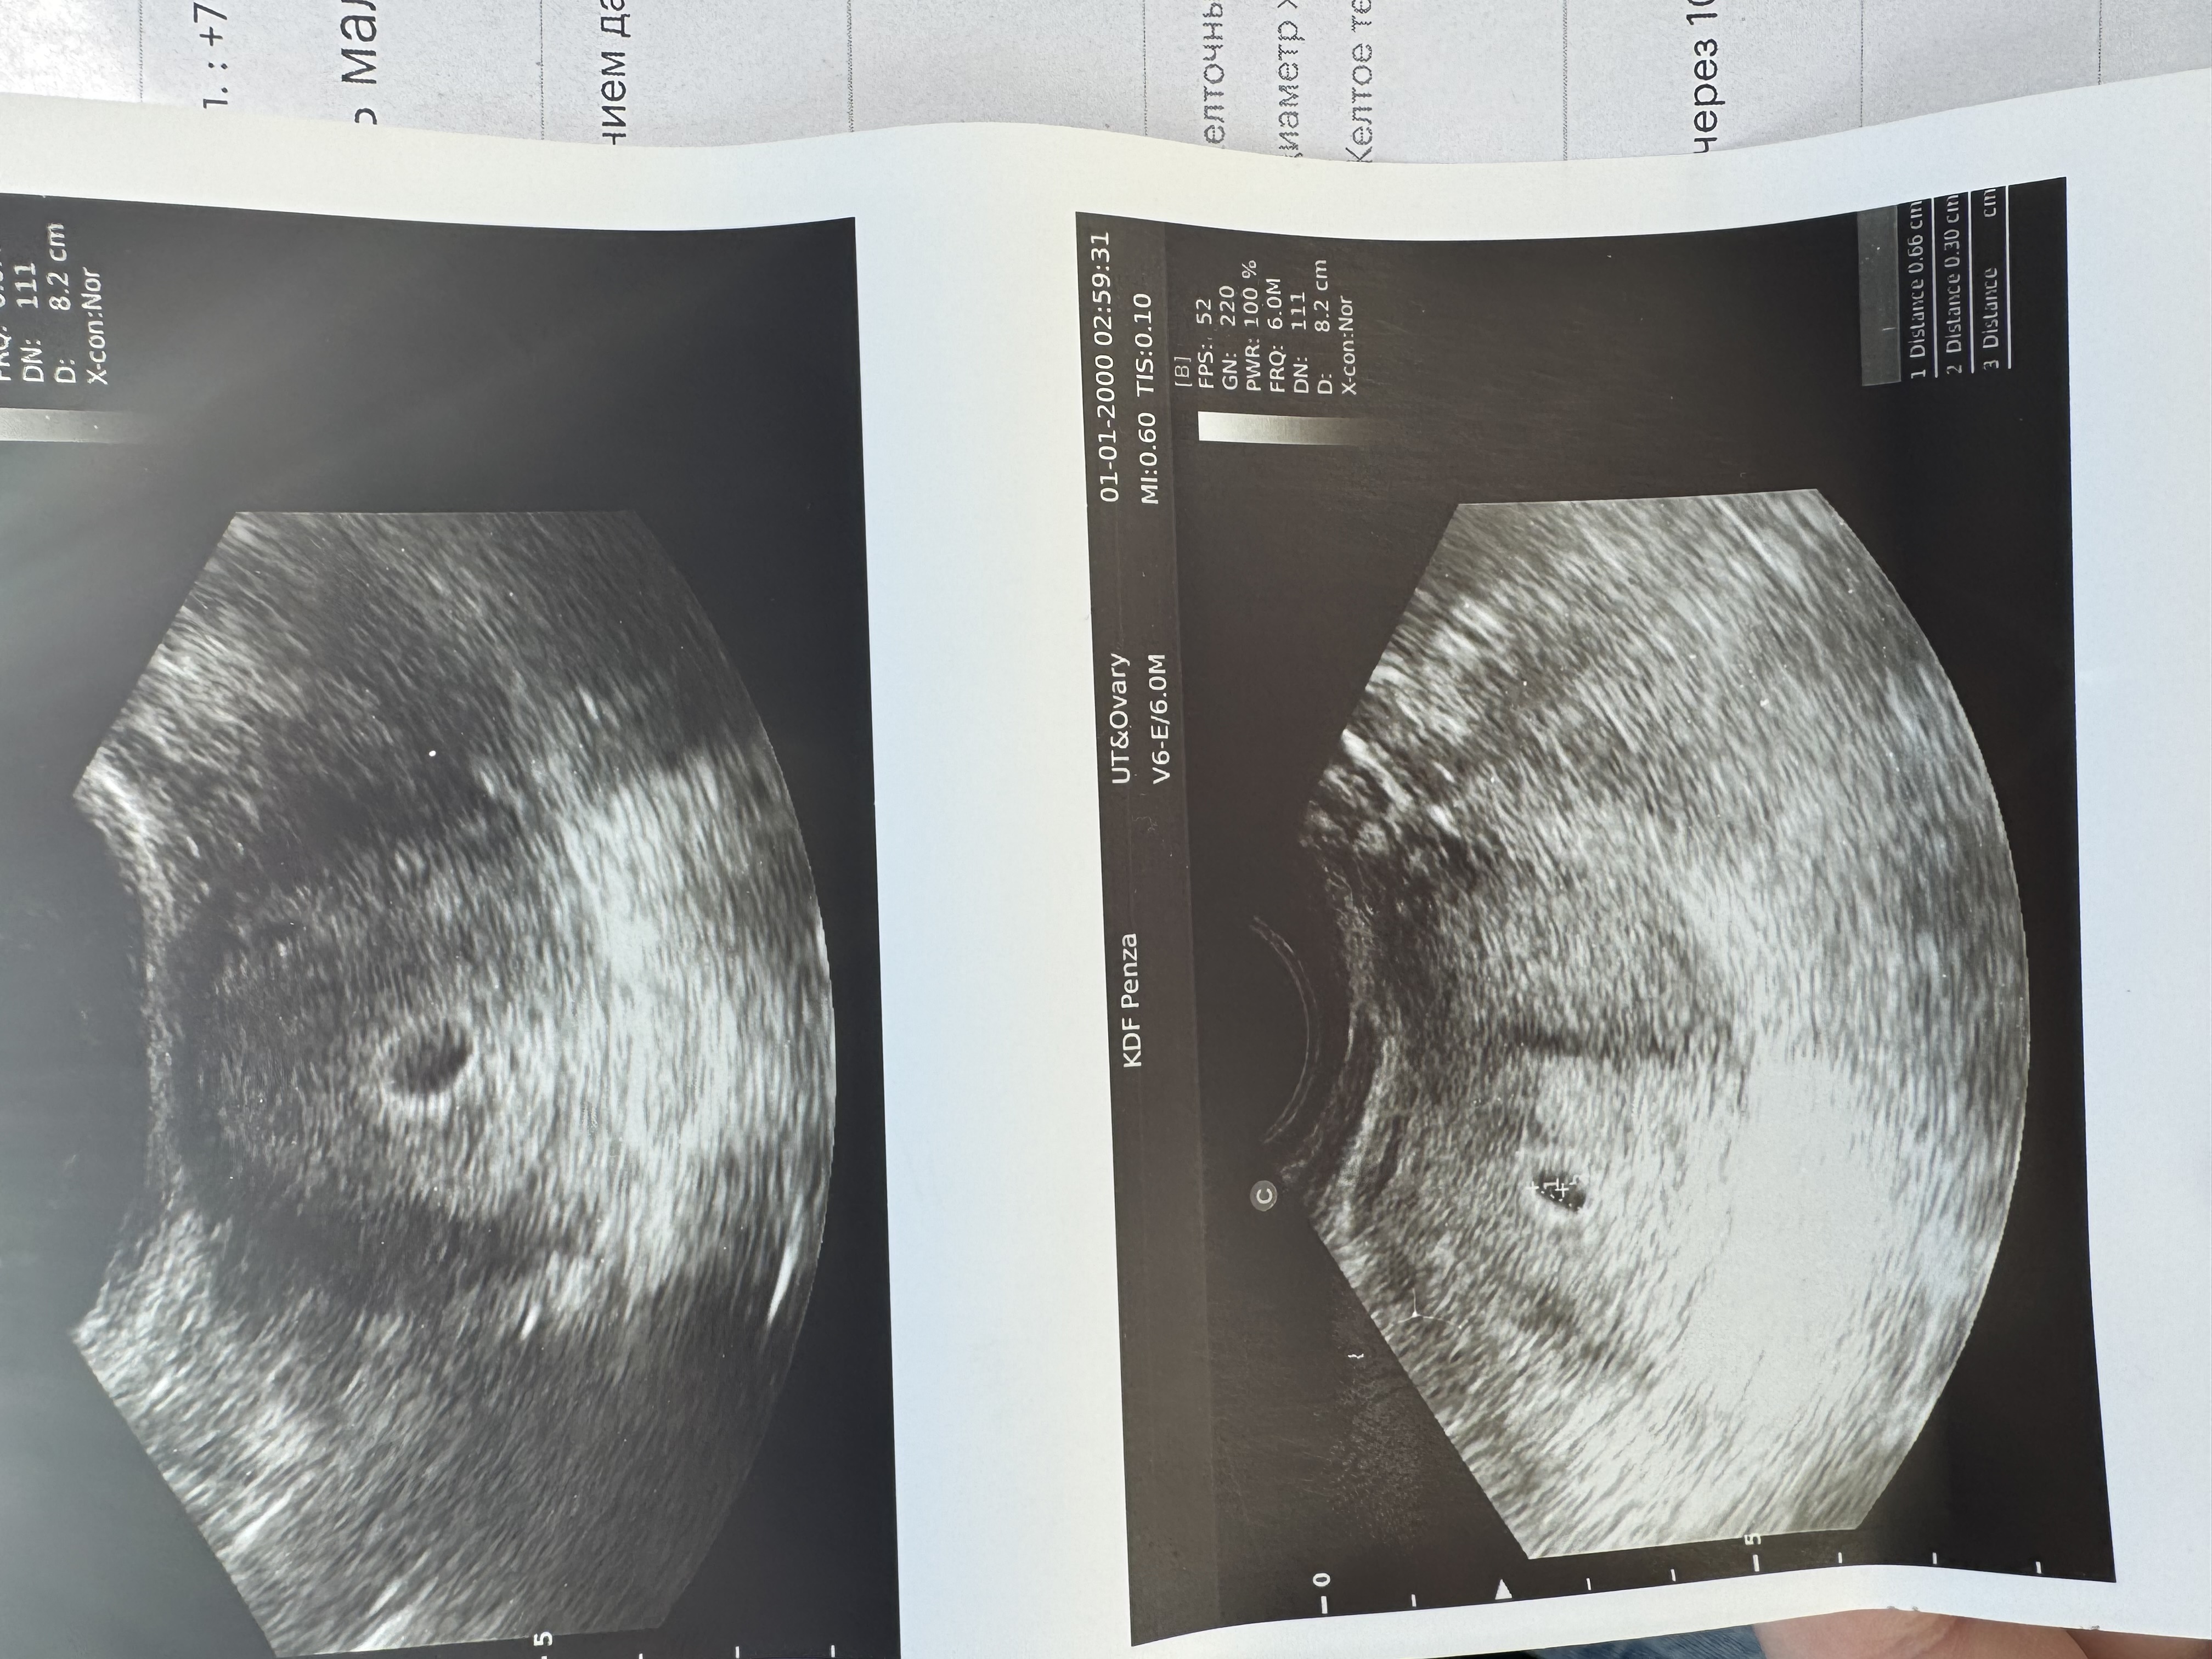

УЗИ 19 ДПП

Была на узи сегодня и у нас пока все отлично 🙏 Нашли и плодное 7 мм и желточный 1,3 мм

Прикрепился хорошо, ни гематом, ни отслоек.

Спросила про срок, она сказала по переносу 3-4 недели, я вот думаю 🤔 А не маловат срок то? Но я что то не спросила 🤷♀️

Поздравляю с маленькой победой. Ждём узи уже с сб+. Мне никогда не считали срок по переносу, хоть я и говорила что ЭКО и крио перенос, все равно считали от первого дня последних М, так сказать в акушерских неделях, измеряли КТР и писали какому сроку соответствует в акушерских неделях, один фиг потом все равно будут считать акушерские недели, я считаю что вот этот вот подсчет по переносу только путает. У меня разница по М и по переносу была день или два всего. А так у вас 5н3д акушерских. У меня на этом сроке было ПЯ 11мм и ЖМ 4мм